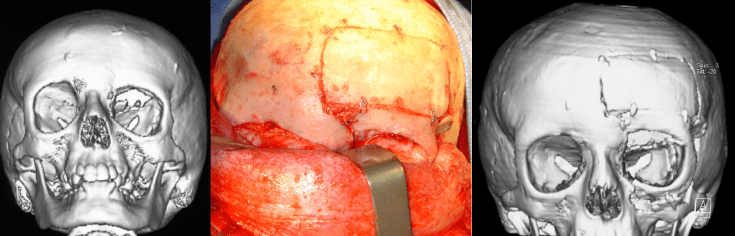

la reconstruction orbitaire pour séquelles morphologiques

- souvent de restaurer une morphologie harmonieuse en cas de déformation en région glabre (Cf. ci-contre)

les différentes interventions